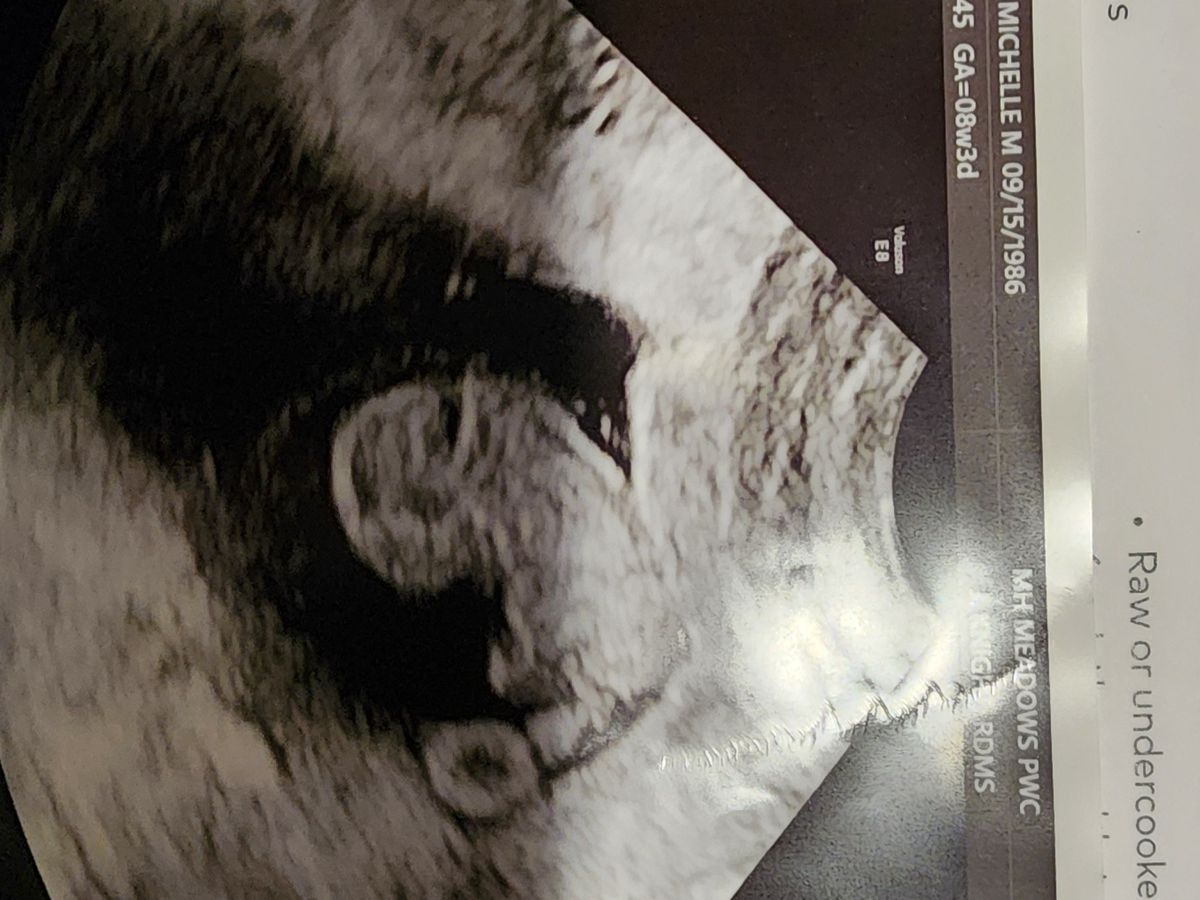

Michelle went to her normal OBGYN check up on March 18 with her husband and daughter to see how baby Matthew Jr was doing. While getting the ultrasound done, the room was silent, her excitement turned to fear, and she was told the worse news for any mother to endure. Baby Matthew no longer had a heart beat. But sadly this was just beginning of the worst week for this poor family.